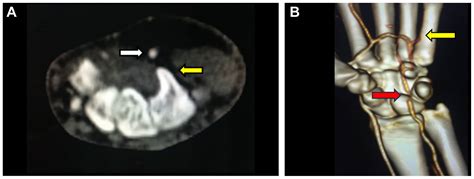

Correct diagnosis is paramount. Because the symptoms overlap with other vascular disorders, physicians usually employ a combination of clinical history and advanced imaging. A physical examination often includes the Allen’s test, which helps assess the patency of the ulnar and radial arteries. If HHS is suspected, the following diagnostic tools are typically utilized:

• Duplex Ultrasound: An excellent initial tool to visualize the blood flow and identify potential blockages or aneurysms.

• CT Angiography (CTA): Provides detailed imagery of the vascular anatomy and is highly effective at identifying aneurysms.

• Magnetic Resonance Angiography (MRA): A non-invasive method to evaluate the integrity of the arterial walls.

• Digital Subtraction Angiography (DSA): Considered the "gold standard" for definitive diagnosis, as it allows for real-time visualization of the blood flow within the hand.